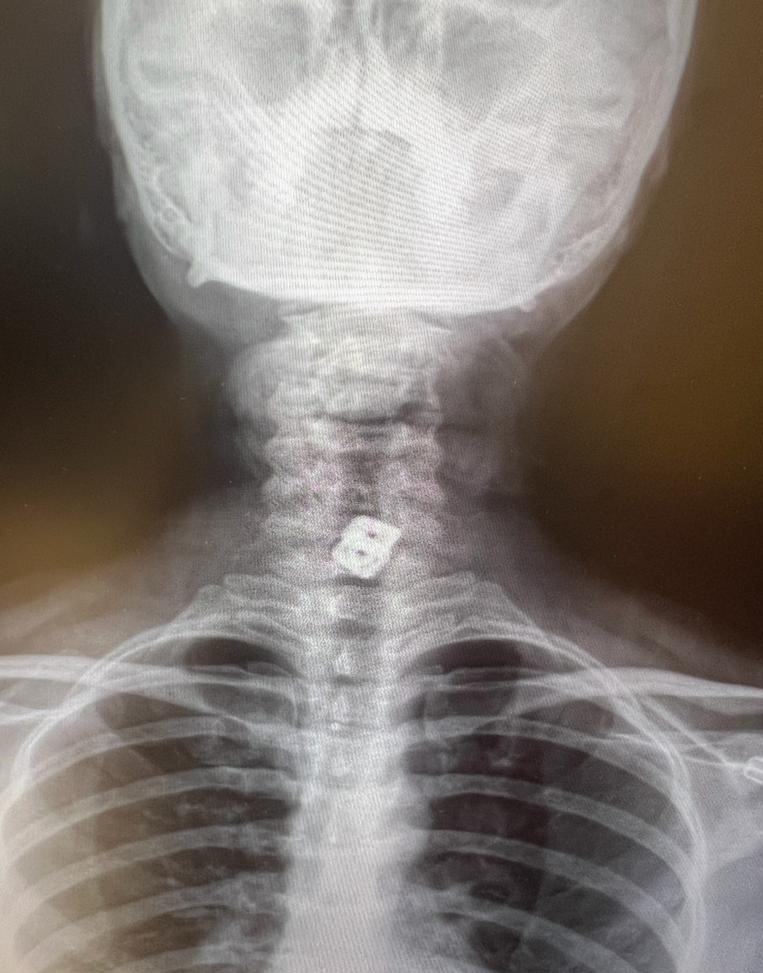

“O hastanede beyin ve sinir cerrahisi uzmanı tarafından ameliyata alınan Sultan Tıraş’ın boyun omuruna konulan iki aparattan biri çıkarılmış, ancak diğerinin yemek borusunu delip mideye indiği belirlenmiş. İlgili hekim bana ulaşarak bilgilendirmeyi yaptı ve hastayı hastanemize sevk etti. Yoğun bakıma alınan hastaya yaptığımız detaylı tetkikler ve klinik değerlendirme sonucu mediyastenit (ciddi göğüs enfeksiyonu) belirlendi. Bu ciddi bir sorun olup, hayati riski yüksektir. En hızlı şekilde tıbbi tedaviye başladık, gastroenteroloji bölümümüzde endoskopi yapıldı. Yemek borusunda oluşan delik ve delikten mideye inen metalik cerrahi aparat görüldü. Göğüs kafesi içinde ciddi bir iltihap ve hava birikimi vardı. Hasta yakınları durum ile ilgili bilgilendirildi, riskler kendileri ile paylaşılarak hastamıza tıbbi müdahale edebilmemiz gerekli onayları alındı.”

“Yaklaşık 6 saat süren bir ameliyat oldu. Hastamıza ilk endoskopik yol ile göğüs orta bölümdeki (mediasten ki bu bölgeye insan hayatının makine dairesi deriz) cerahat boşaltılıp tahliye edildi. Daha sonra boyun bölgesindeki biriken iltihap temizlendi. Yemek borundaki 2 cm’lik perforasyon (delik) tespiti ve tamiri yapıldı” diyen Prof. Dr. Elbeyli, şu bilgileri paylaştı:

Hastanın endoskopik incelemesinde yabancı cisim tespit edildi

“Endoskopi sırasında hastanın midesinde metalik bir oluşuma benzer yabancı cisim ile yemek borusunda ülser görünümü izledik. Lezyon bölgesi belirlendikten sonra hastamızın tedavisi için Göğüs Cerrahisi Bölümümüze durumu ilettik. Prof. Dr. Levent Elbeyli Hocamız hastamızın sağlığına kavuşması için gerekli tedaviyi planlayarak, başarılı bir operasyonla sonuca ulaştı. Emeği geçen herkese teşekkür ediyorum. Hastamızı sağlıklı bir ömür diliyorum.”